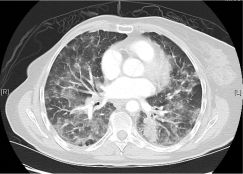

一位77岁的女性患有EPS15-NTRK1 IV期非小细胞肺癌,我们可以看到她的双肺满是病灶,并且出现了肝脏和脑转移,可以说是非常非常晚期了,

肺靶病变达到缓解,我们可以明显的看到前后的图像,病灶明显缩小了,

脑转移病变显示缩小了95%!

初始, 2018年6月             3周期 2018年8月